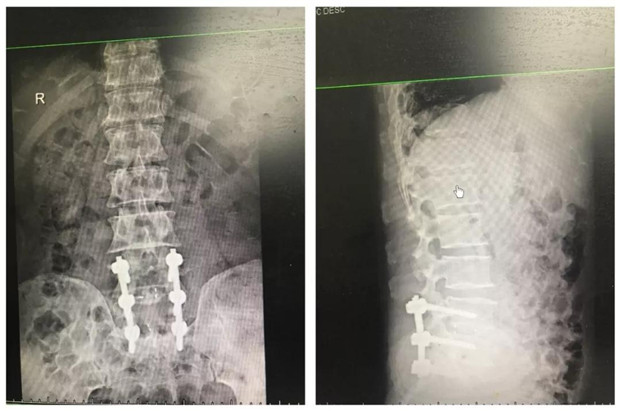

2节段腰椎间盘突出伴椎管狭窄钉棒系统Cage植骨内固定术